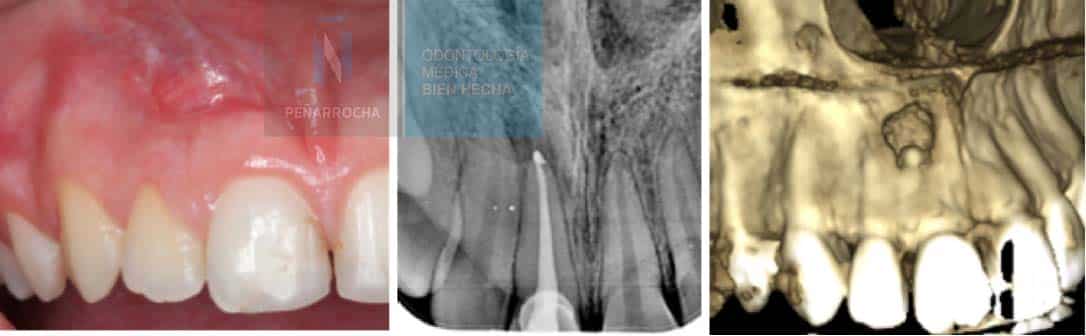

En estas imágenes se observa una lesión radiotransparente alrededor del ápice del diente, con una endodoncia bien hecha en principio, pero fracasada finalmente, y su posterior curación radiográfica tras una cirugía periapical. En todo caso, es importante que un especialista en endodoncia o cirugía bucal evalúe la radiografía para determinar el estado del tratamiento.